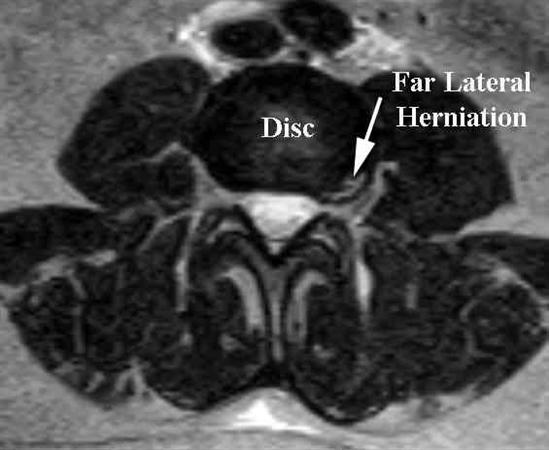

DISCUSSION: The clinical scenario describes a patient with central cord syndrome, resulting in an injury to his lateral corticospinal tract. Figures A through C show a spondylytic spine with central narrowing and CSF effacement that is worse at the C4-5 level. The lateral corticospinal tract is the main descending motor tract (Illustration A). Its anatomic position places the upper extermity motor tracts at greater risk than the lower extremity tracts. As such, injury to the lateral corticospinal tract is characterized by upper greater than lower extremity involvement and motor deficits being more pronounced than sensory deficits.